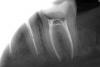

natalia sado Опубликовано 3 ноября, 2012 Поделиться Опубликовано 3 ноября, 2012 Здравствуйте. Моя ситуация такова: зуб 37 был пролечен летом, нерв не трогали, поставили пломбу. Но! впоследствии появилась боль при накусывании (т.е. жить мне он не мешал, болеутоляющие я не пила, но понимала, что корочку хлеба он жевать не может. Иду к врачу, говорит: "я знал, потому как пульпа была слишком близко, пожалел тебя и зуб, а надо было депульпировать" Что он и сделал. (см снимки 1 и 2). Также он решил, что нужен штифт, но это позже, нужно чтобы прошло время. Время это как раз нам было очень на руку, потому как сразу от него я пошла в кабинет хирурга удалять соседнюю восьмерку,от которой накакуне просто отвалился кусок. Я еще помню подумала, что может оно как-то не очень сочетать эндодонтическое лечение и удаление соседнего зуба, тем более что зуб мудрости был ого-го!! а удалял мне его хирург 1.5 часа (врач кстати отличный), но возможно это всего лишь женская привычка все преувеличить Пошла я восвояси заживлять лунку, с временной пломбой на 37 зубе, ожидающего штифта и реставрации. Дело было 9 сентября.В 20х числах сентября я была на осмотре у хирурга, т.к. восьмерка у меня заживать не хотела, промучилась я с осложнениями, но не так все просто - опять напасть: За это время замечала снова болевые ощущения на этой 7ке, пробовала пожевать, когда лунка позволила-те же симптомы, все точно также, опять на грубую пищу такая реакция (надо сказать, что эта симптоматика вообще стала мне родной за последнее время, это был не первый зуб со схожими проблемами). Тут же заруливаю к своему лечащему. Сделали снимок (3), посовещался с коллегами- все в один голос: неееееет!!! не может быть!! чему тут болеть, запломбировано все идеально, это оседает материал. ну ок! только вот неделю назад надоело мне ждать, пока "он осест" и я пошла с твердым намерением сделать снимок (кстати действительно настояла, опять пытались переубедить).И вот результат: фото 4! даже я вижу, с каналами то проблема!! уже и мой врач не отрицает , но хотелось бы понять, судя по динамике снимков, что же произошло, почему, и что тут теперь вытворять?Пожалуйста, выскажитесь, очень важны ваши советы и мнения. Уже обращалась к вам недавно по поводу синуслифта, помогли настроиться и принять решение. Очень не хочется вслепую вершить судьбу своих зубов. Ссылка на комментарий

natalia sado Опубликовано 3 ноября, 2012 Автор Поделиться Опубликовано 3 ноября, 2012 Вот только фото разместились четко наоборот))Чтобы соблюсти хронологию снимков, отсчет по номерам, кот. я указала в тексте, ведем справа налево Ссылка на комментарий

DmitrySH Опубликовано 3 ноября, 2012 Поделиться Опубликовано 3 ноября, 2012 Были сложности на этапе обработки и дезинфекции каналов. Снимок до начала лечения интересно посмотреть. Ссылка на комментарий

Magdalena Опубликовано 3 ноября, 2012 Поделиться Опубликовано 3 ноября, 2012 За период от первого до последнего снимка на корнях появилось воспаление. Причины могут быть 1. Погрешности в обработке каналов, лечение без изоляции зуба коффердамом ( могла слюна попасть с микробами) 2..Впечатление, что на снимке с инструментами в дистальном корне (ближе к 8 зубу) есть еще один канал. Уточнить до перелечивания можно сделав 3д-томограмму. Ссылка на комментарий